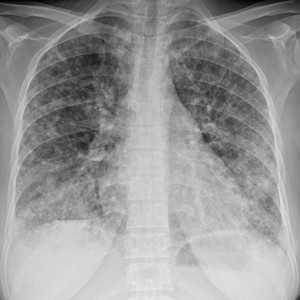

Слева - рак почки с метастазами в легкие, прогноз в данном случае неблагоприятный ввиду метастатического плеврита и дыхательной недостаточности. Определяются очаги с обеих сторон. Справа - мелко- и среднеочаговая диссеминация при раке печени.

Множественные гематогенные вторичные узлы при раке почки, компьютерная томография (КТ).